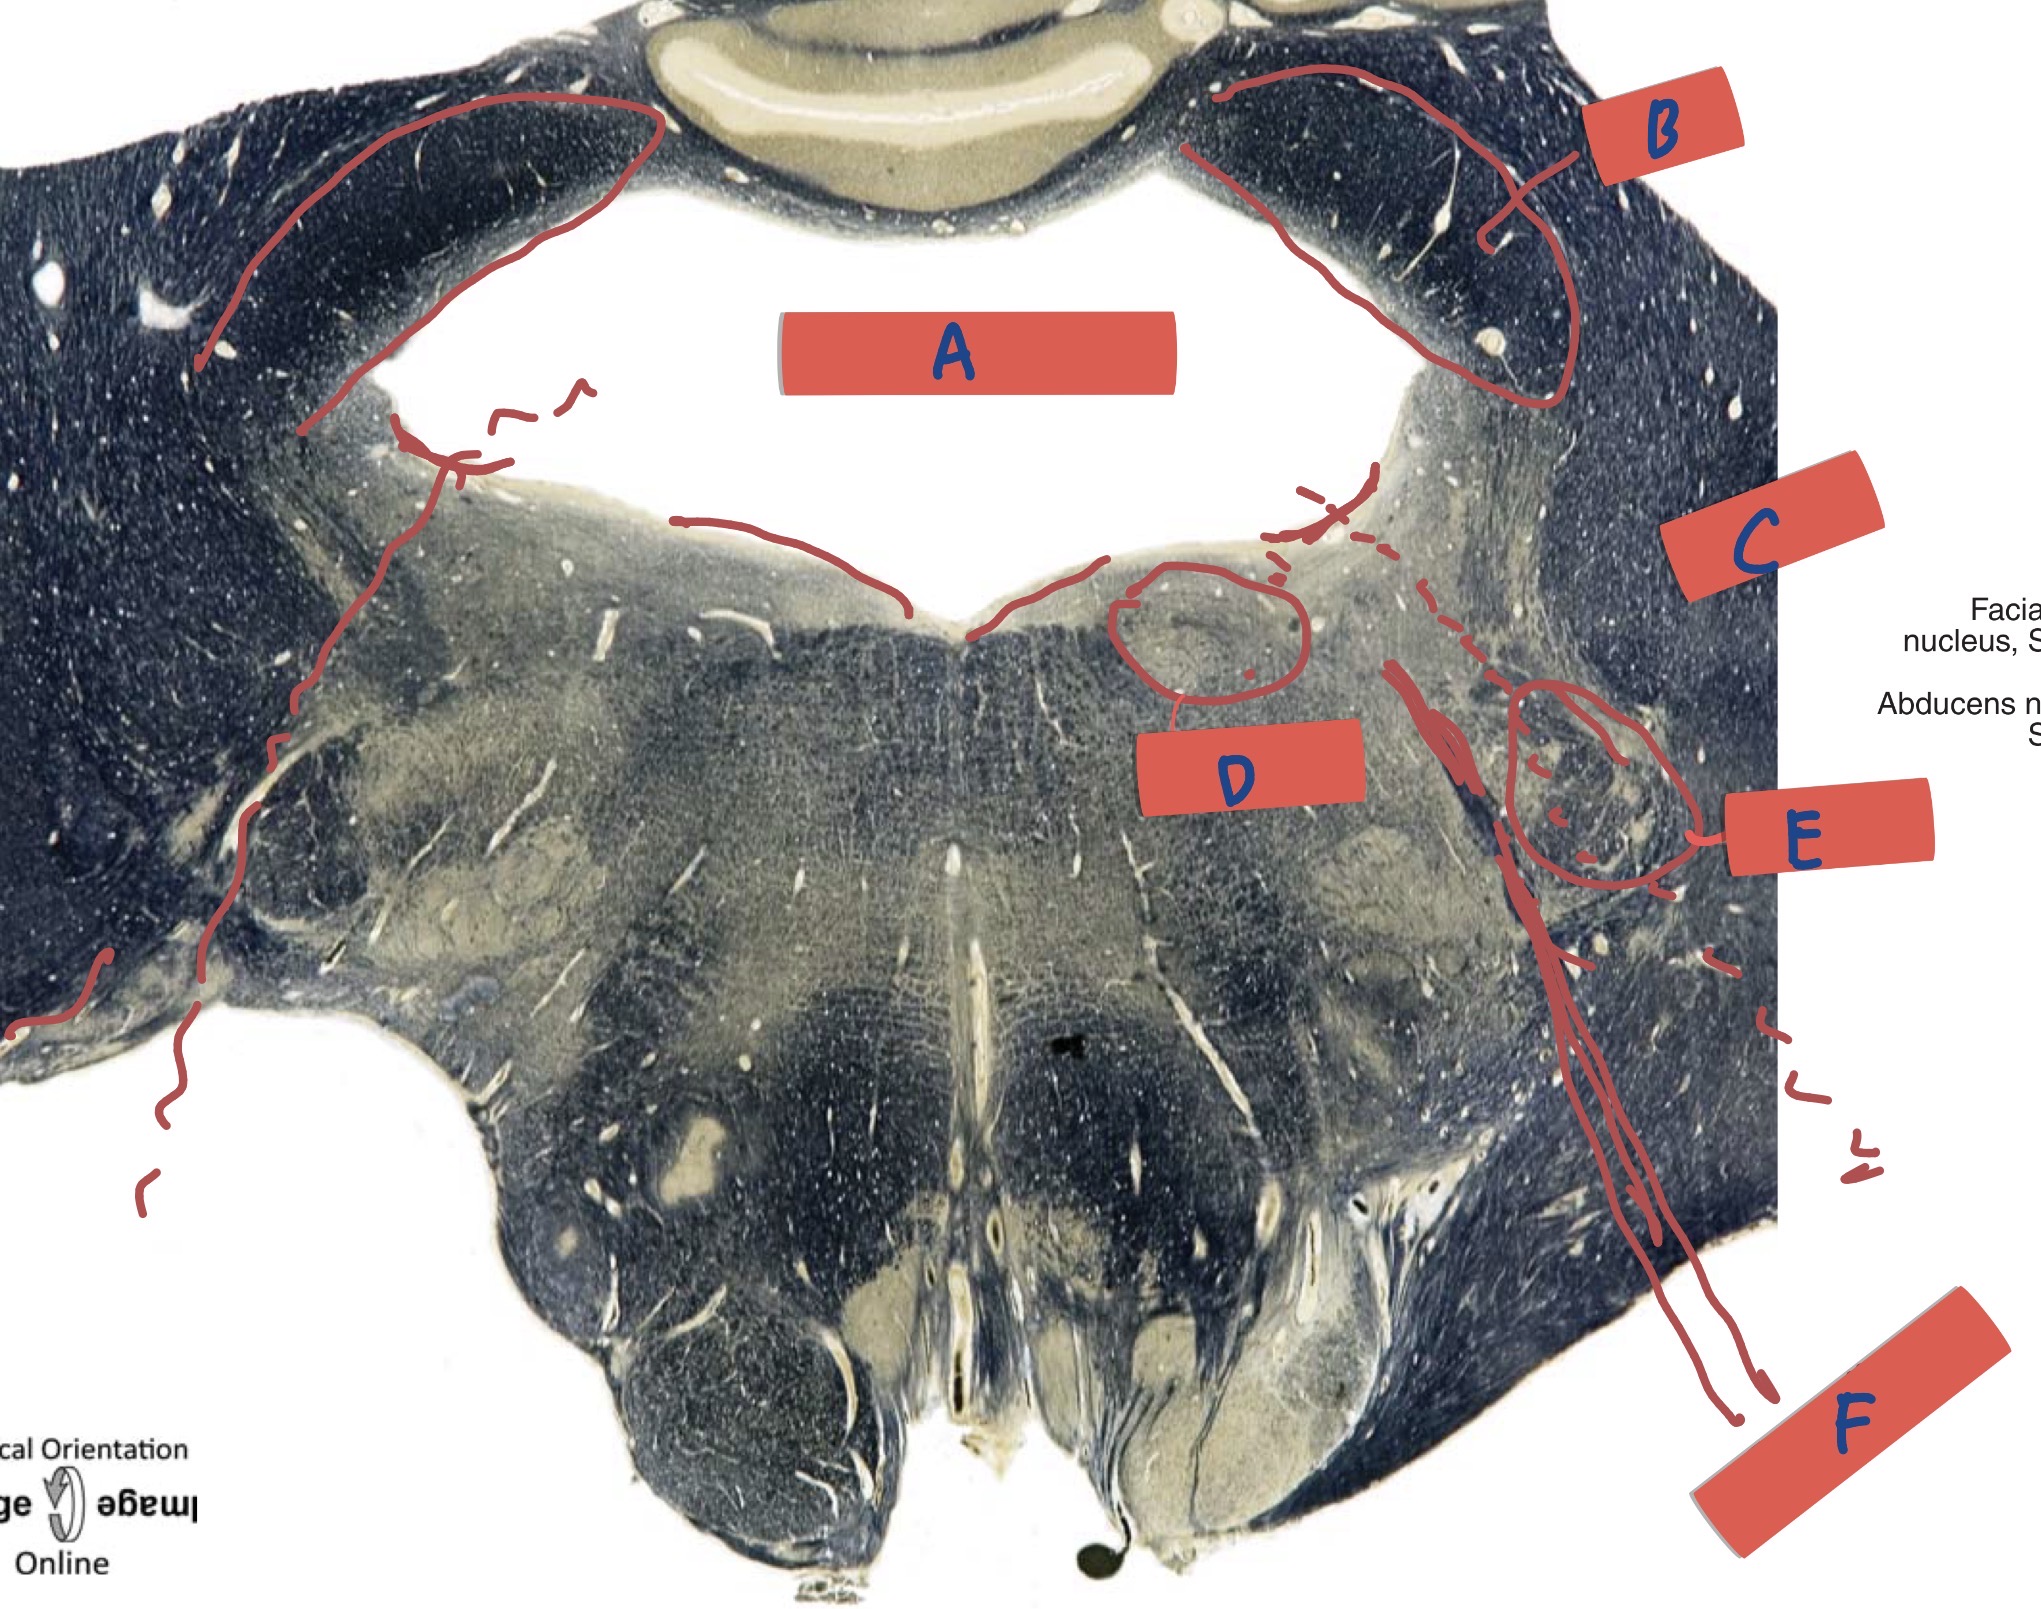

What is A?

Mesencephalic tract

Whats is B?

CN V nerve, motor, and sensory nucleus

What is C?

Superior cerebellar peduncle

What is D?

Internal genu of facial nerve

What is E?

Facial nerve

What is F?

Medial lemniscus

What level is this?

Caudal pons